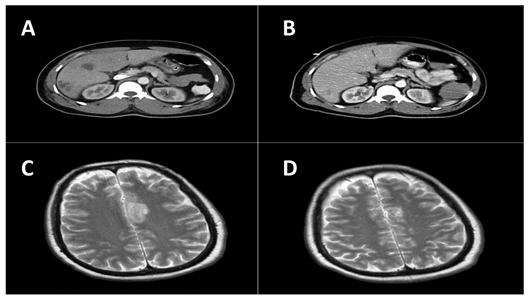

On day eight, he was airlifted to Mount Sinai Medical Center, a tertiary care facility in Miami Beach, Florida, for further management. Upon arrival, he was afebrile (T 98.0°F), bradycardic (38 beats per minute), intubated, and unresponsive. Physical examination revealed diffuse rhonchi bilaterally and right upper quadrant tenderness. Endopthalmitis was specifically sought and was not present in this patient. The remainder of the physical examination was unremarkable. Blood cultures drawn at this time were negative. The initial working diagnosis was dengue fever. Subsequently, a computed tomographic (CT) scan of the abdomen revealed multiple liver abscesses with possible necrosis with the largest measuring abscess (Figure 1a). Entamoeba titers were negative. Blood cultures drawn three days after admission grew K. pneumoniae. The susceptibility pattern for the K. pneumoniae was not unusual. It was resistant to ampicillin and intermediate to ampicillin/sulbactam. It was sensitive to the cephalosporins (cefazolin, cefotaxime, and cefepime), the fluoroquinolones (ciprofloxacin, levofloxacin), the aminoglycosides (amikacin, gentamicin, and tobramycin), meropenem, pipercillin/tazobactam and trimethoprim/sulfa. At this point, the patient was started on meropenem. The initial CT scan of the brain done on arrival to Mount Sinai was negative. However, follow-up CT of the brain seven days later showed a 2.7 cm abscess located in the frontal lobe. Two days later an additional lesion developed in the left parietal region (Figure 1c).

A and B are computed tomography (CT) scans of the abdomen. (a) Before treatment showing multiple liver abscesses with the largest measuring 3.9 cm. (b) After treatment showing improved resolution. C and D are CT scans of the brain. (c) Nine-days after arrival an additional lesion developed in the left parietal region. (d) After treatment showing improved resolution.

Int J Med Sci Image

The patient underwent CT-guided drainage and biopsy of the largest liver abscess. The biopsy demonstrated abundant acute and chronic inflammation with surrounding necrosis consistent with a liver abscess. A sample aspirated from the liver was submitted for culture. The Gram stain of the material showed many neutrophils, but no organisms. On the third day of culture, there was growth of a mucoid Gram-negative lactose-fermenting bacillus identified as Klebsiella pneumoniae. This isolate, henceforth referred to as FIUMS1, had a characteristic hyperviscous phenotype as demonstrated by the formation of elongated (>5 mm) mucoviscous strings when a loop was passed through a colony. Subsequently, his antibiotic was changed to ceftriaxone. Three weeks after admission, he became afebrile, was extubated, and the brain and liver lesions improved radiologically (Figure 1b and 1d). He returned to Saint Kitts where he remained clinically stable and completed six weeks of antibiotic treatment.